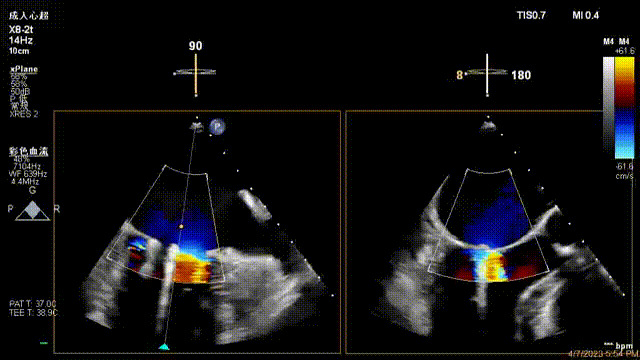

接受治療的是一例器質(zhì)性重度二尖瓣反流(DMR)患者,主訴“反復(fù)活動后胸悶,氣促3年余”。術(shù)前超聲顯示,雙房增大,二尖瓣脫垂伴重度反流,輕度三尖瓣反流,輕度肺高壓,升主動脈增寬。手術(shù)經(jīng)股靜脈-房間隔入路,采用全身麻醉插管,在TEE和DSA引導(dǎo)下完成房間隔穿刺。置入JensClip瓣膜夾系統(tǒng)后,在左房調(diào)整瓣膜夾的位置和軸向,后進入左室,在TEE引導(dǎo)下捕捉二尖瓣前后瓣葉,并關(guān)閉瓣膜夾。經(jīng)TEE反復(fù)確認手術(shù)效果后最終鎖定并釋放瓣膜夾。術(shù)后即刻超聲顯示瓣膜夾位置穩(wěn)定,功能良好,術(shù)前二尖瓣反流4+,術(shù)后0反流,肺靜脈逆流和左房壓都顯著好轉(zhuǎn),手術(shù)圓滿成功(以上數(shù)據(jù)都來源于醫(yī)院的臨床記錄)。術(shù)后患者狀態(tài)良好,目前已安排出院。

術(shù)前超聲提示二尖瓣重度反流

術(shù)后超聲顯示二尖瓣反流消失,瓣膜夾穩(wěn)定

出院前隨訪超聲